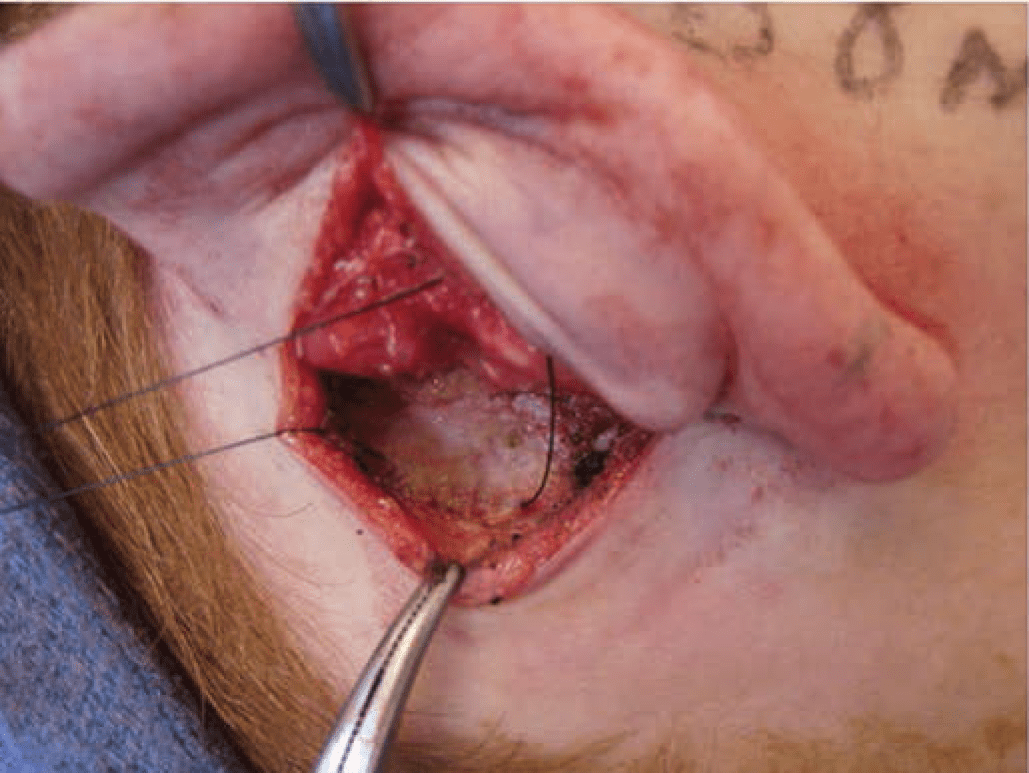

Correction of Earlobe Prominence. Earlobe prominence is not corrected by the above maneuvers. In fact, these maneuvers may increase the prominence of the earlobe, making earlobe repositioning the most difficult and neglected part of the procedure. An auricle that has been repositioned in its upper two thirds but still has a prominent lobule will appear just as abnormal and disharmonious as the original deformity (Figure 49.7). It has been said that suturing the tail of the helical cartilage to the concha will correct earlobe prominence. Unfortunately, the tail of the helix does not extend into the lobule and setting it back does not reliably set back the earlobe. Other authors have described techniques involving skin excision and sutures between the fibrofatty tissue of the lobule and the tissues of the neck. The best technique in the author’s experience is the technique described by Gosain,5 or a variation thereof, in which a small amount of skin is excised on the medial surface of the earlobe. When this defect is closed with sutures, a bite of the undersurface of the concha is taken, which pulls the earlobe toward the head.